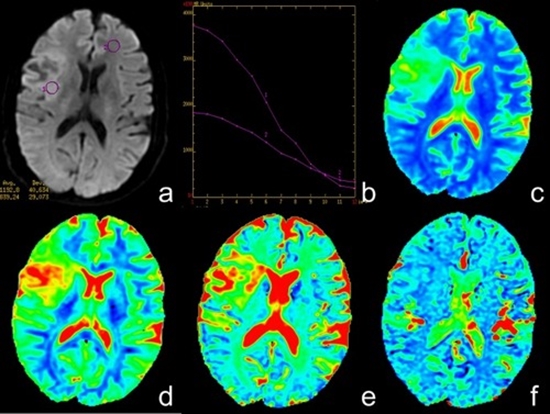

Diagnostic value of Intra Voxel Incoherent Motion images using MRI based on deep learning analysis to predict glioma genotype